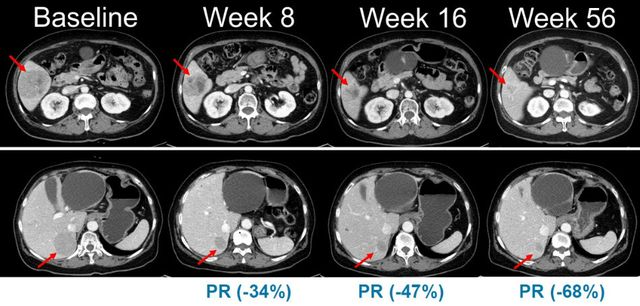

벨바라페닙과 코비메티닙 병용요법 임상시험에서 시간 경과에 따른 병변 변화가 관찰된 복부 CT 영상 / 미국임상종양학회(ASCO) 2021 구연 발표